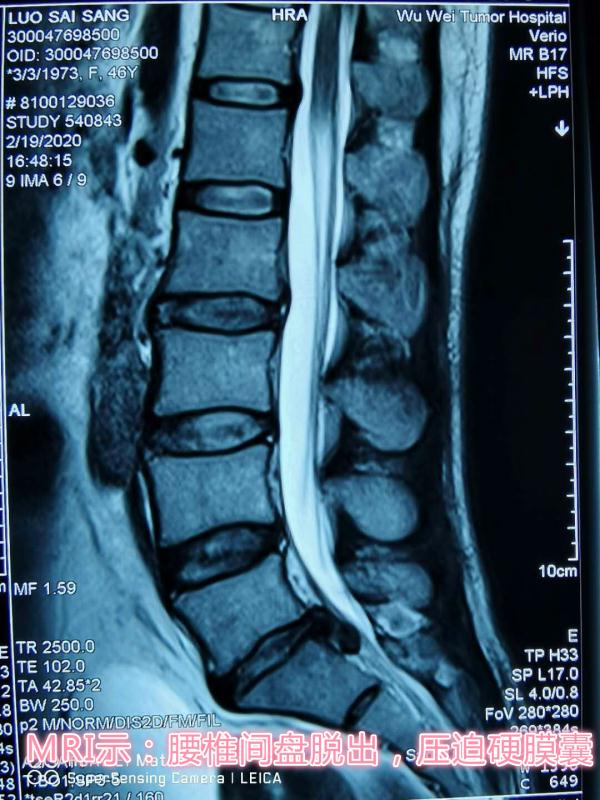

患者,女性,47岁,左下肢疼痛伴麻木1年,加重两月。入院后,骨科医护团队立即完善相关检查,仔细察看患者病情发展情况,为其制定了精准的治疗方案,同时向患者及家属详细讲解了手术的优势及术后的注意事项,患者及家属表示理解并同意手术。术中一切顺利,术后患者次日即可下地活动,大大缩短了传统Tlif术后需卧床三月的修复时间。